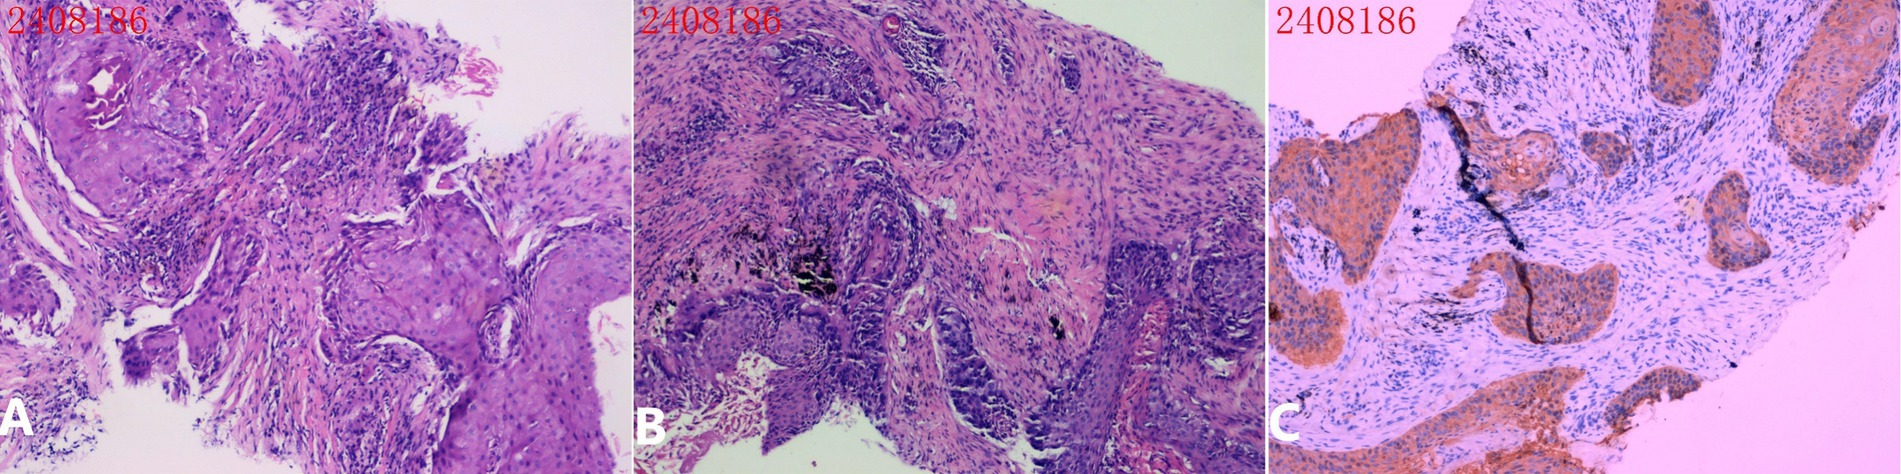

Intercostal artery (ICA) injury during CT-guided percutaneous transthoracic needle biopsy (PTNB) is a rare but potentially severe complication. This case report describes a cautious approach for detecting and managing suspected ICA injury using a coaxial needle system. During PTNB in a 71-year-old male with lung cancer, ICA injury was detected through blood aspiration during needle withdrawal. Management involved immediate cessation of withdrawal, slight needle advancement for mechanical hemostasis, and serial monitoring, achieving hemostasis without requiring additional invasive interventions. Literature review of cases from 2018 to 2024 revealed that current management approaches vary based on severity, with a 30% mortality rate among reported cases. Most ICA injuries are detected post-procedurally rather than intraoperatively. Traditional interventions range from conservative treatment to transcatheter arterial embolization (TAE) or thoracotomy. This approach suggests a potential stepwise method for managing suspected ICA injury that might reduce complications and minimize the need for invasive interventions. As a single case report representing hypothesis-generating evidence, this observation requires further validation through collaborative experience from other operators when similar circumstances arise. The case demonstrates an exploratory approach for managing ICA injury during PTNB, particularly relevant in resource-limited settings where interventional radiology services may not be immediately available.